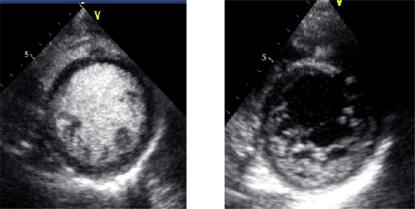

Bedside echocardiography in emergency room (ER) or in intensive care unit (ICU) is an important tool for managing critically ill patients, to obtain a timely accurate diagnosis and to immediately stratify the risk to the patient's life. It may also render invasive monitoring unnecessary. In these patients, contrast echocardiography may improve quality of imaging and also may provide additional information, especially regarding myocardial perfusion in those with suspected coronary artery disease. This article focuses on the principle of contrast echocardiography and the clinical information that can be obtained according to the most frequent presentations in ER and ICU.

急诊室(ER)或重症监护病房(ICU)中的床旁超声心动图是管理危重症患者的重要工具,有助于及时准确地做出诊断,并立即对患者的生命风险进行分层。它还可能使侵入性监测变得不必要。对于这些患者,超声造影可提高成像质量,还可能提供额外信息,尤其是对于疑似冠心病患者的心肌灌注情况。本文重点介绍超声造影的原理以及根据急诊室和重症监护病房中最常见的表现所能获得的临床信息。